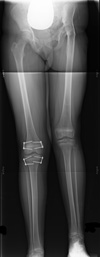

In children who are still growing, epiphysiodesis can be used to slow down or stop growth at one or two growth plates in the longer leg.

It is a relatively simple surgical procedure that can be performed in one of two ways:

The procedure is performed through very small incisions in the knee area, using x-rays for guidance. Proper timing is critical. The goal is to reach equal leg length by the time growth normally ends—usually in the mid to late teenage years.

Disadvantages of epiphysiodesis include:

X-ray of epiphysiodesis. Metal plates with screws have been placed around growth plates in both the femur and tibia to temporarily restrict growth.

Reproduced from Pierz K: Limb length discrepancy in children. Orthopaedic Knowledge Online Journal 2011; 9(6). Accessed May 2016.